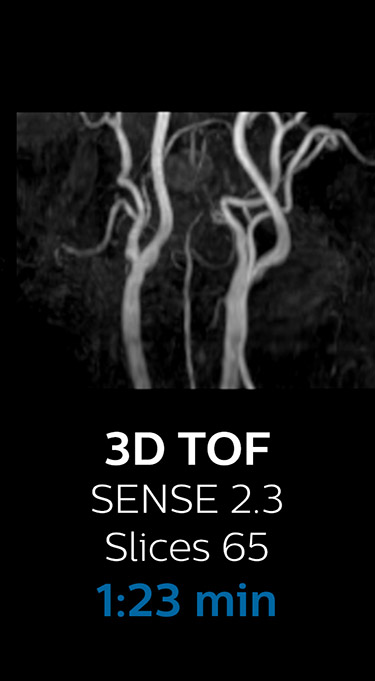

Fast MRI of cervical spine

With Compressed SENSE, the scan time for the routine cervical spine examination at KNC was reduced from 13:11 to 9:52 minutes, which corresponds to 25% reduction.

MRI examination of the cervical spine with Compressed SENSE

Ingenia 3.0T CX

Scan time 9:52 min. (was 13:11 min. without Compressed SENSE)